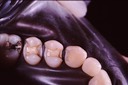

Ted Ramage Slides - Class III restorations on cuspids